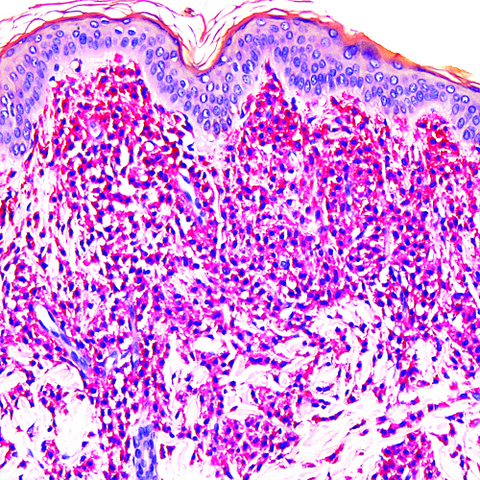

Microscopic (histologic) description

- Within the macules and plaque, mast cells are predominantly in papillary dermis

- Mast cells are round or spindle shaped with abundant eosinophilic cytoplasm, distinct cytoplasmic boundaries, large pale nuclei

- Eosinophils are often present

- Also edema of papillary dermis, subepidermal vesiculation

- Bullous mastocytosis may be diagnosed by Tzank smear; infiltrate may be slight and perivascular

- In telangiectasia macularis eruptive perstans, features may be subtle, with increased mast cells around dilated superficial capillaries, basal cell hyperpigmentation of overlying epidermis, superficial lymphohistiocytic infiltrate

Microscopic (histologic) images